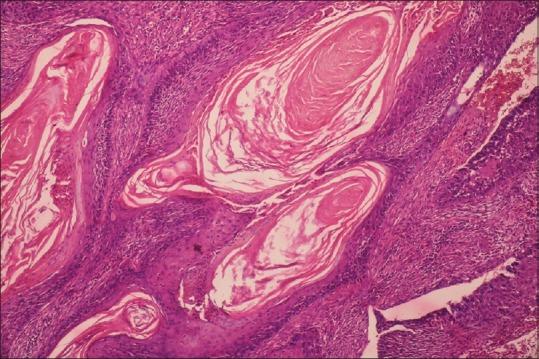

To study mutated/wild type p53 expression using immunohistochemistry and detect HPV-16 presence using polymerase chain reaction (PCR), in OSCC and correlating their expression.

Immunohistochemical staining for p53 molecule in 24 sections of OSCC followed by DNA extraction of the cases using qiagen extraction kit and subsequent HPV-16 detection using PCR technique.

Out of 24 cases of OSCC, twenty cases were positive for P 53 expression and four cases were negative for P 53 expression. Out of the four negative cases, one case was detected positive for HPV-16.